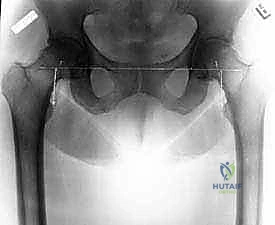

- التصوير الشعاعي الدقيق: إجراء صور أشعة سينية (X-rays) بوضعيات محددة، وفي بعض الحالات المعقدة يتم طلب أشعة مقطعية (CT Scan) أو رنين مغناطيسي (MRI) لعمل تخطيط ثلاثي الأبعاد للعملية واختيار مقاسات المفصل الصناعي بدقة متناهية.